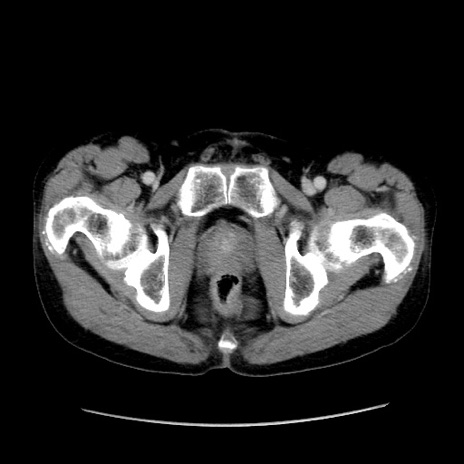

症例37(横断像)

【症例】40歳代 男性

【主訴】腹痛

【現病歴】4時間ほど前に電車に乗車中に臍部上より腹痛出現。徐々に増悪し起立困難となり、救急外来受診。生ものは数日食べていない。今朝お雑煮を食べた。

【身体所見】BT 36.8℃、BP 117/84mmHg、HR 91/min、SpO2 97%、苦悶様、腹部:臍上部広範囲圧痛あり、反跳痛±

【データ】WBC 8100、CRP 0.03